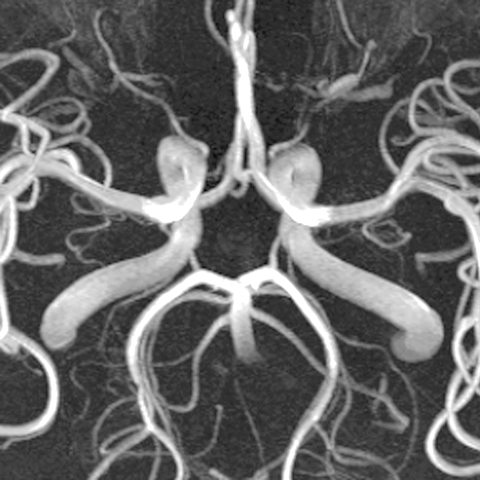

Circle of Willis (MRA) [5 of 6]